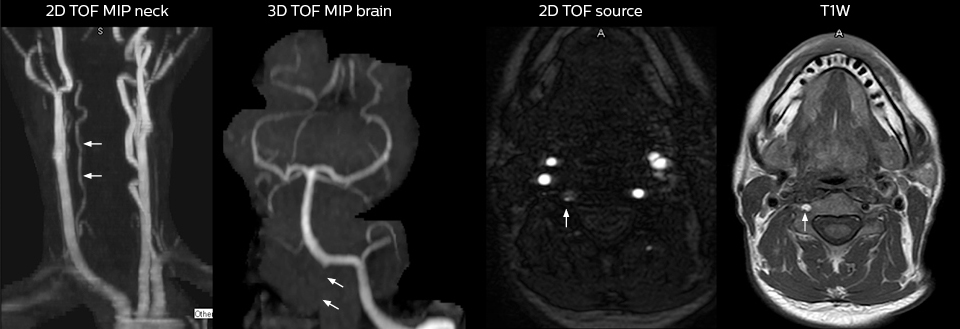

Routineuntersuchung der Halswirbelsäule

Dieser Patient wurde mit Kopfschmerzen vorstellig, die sich bei einer Flexion des Nackens verschlimmerten, und wir sehen hier eine Chiari-Malformation vom Typ I mit niedrig liegenden Kleinhirntonsillen sowie degenerativen zervikalen, thrombolytischen Veränderungen.